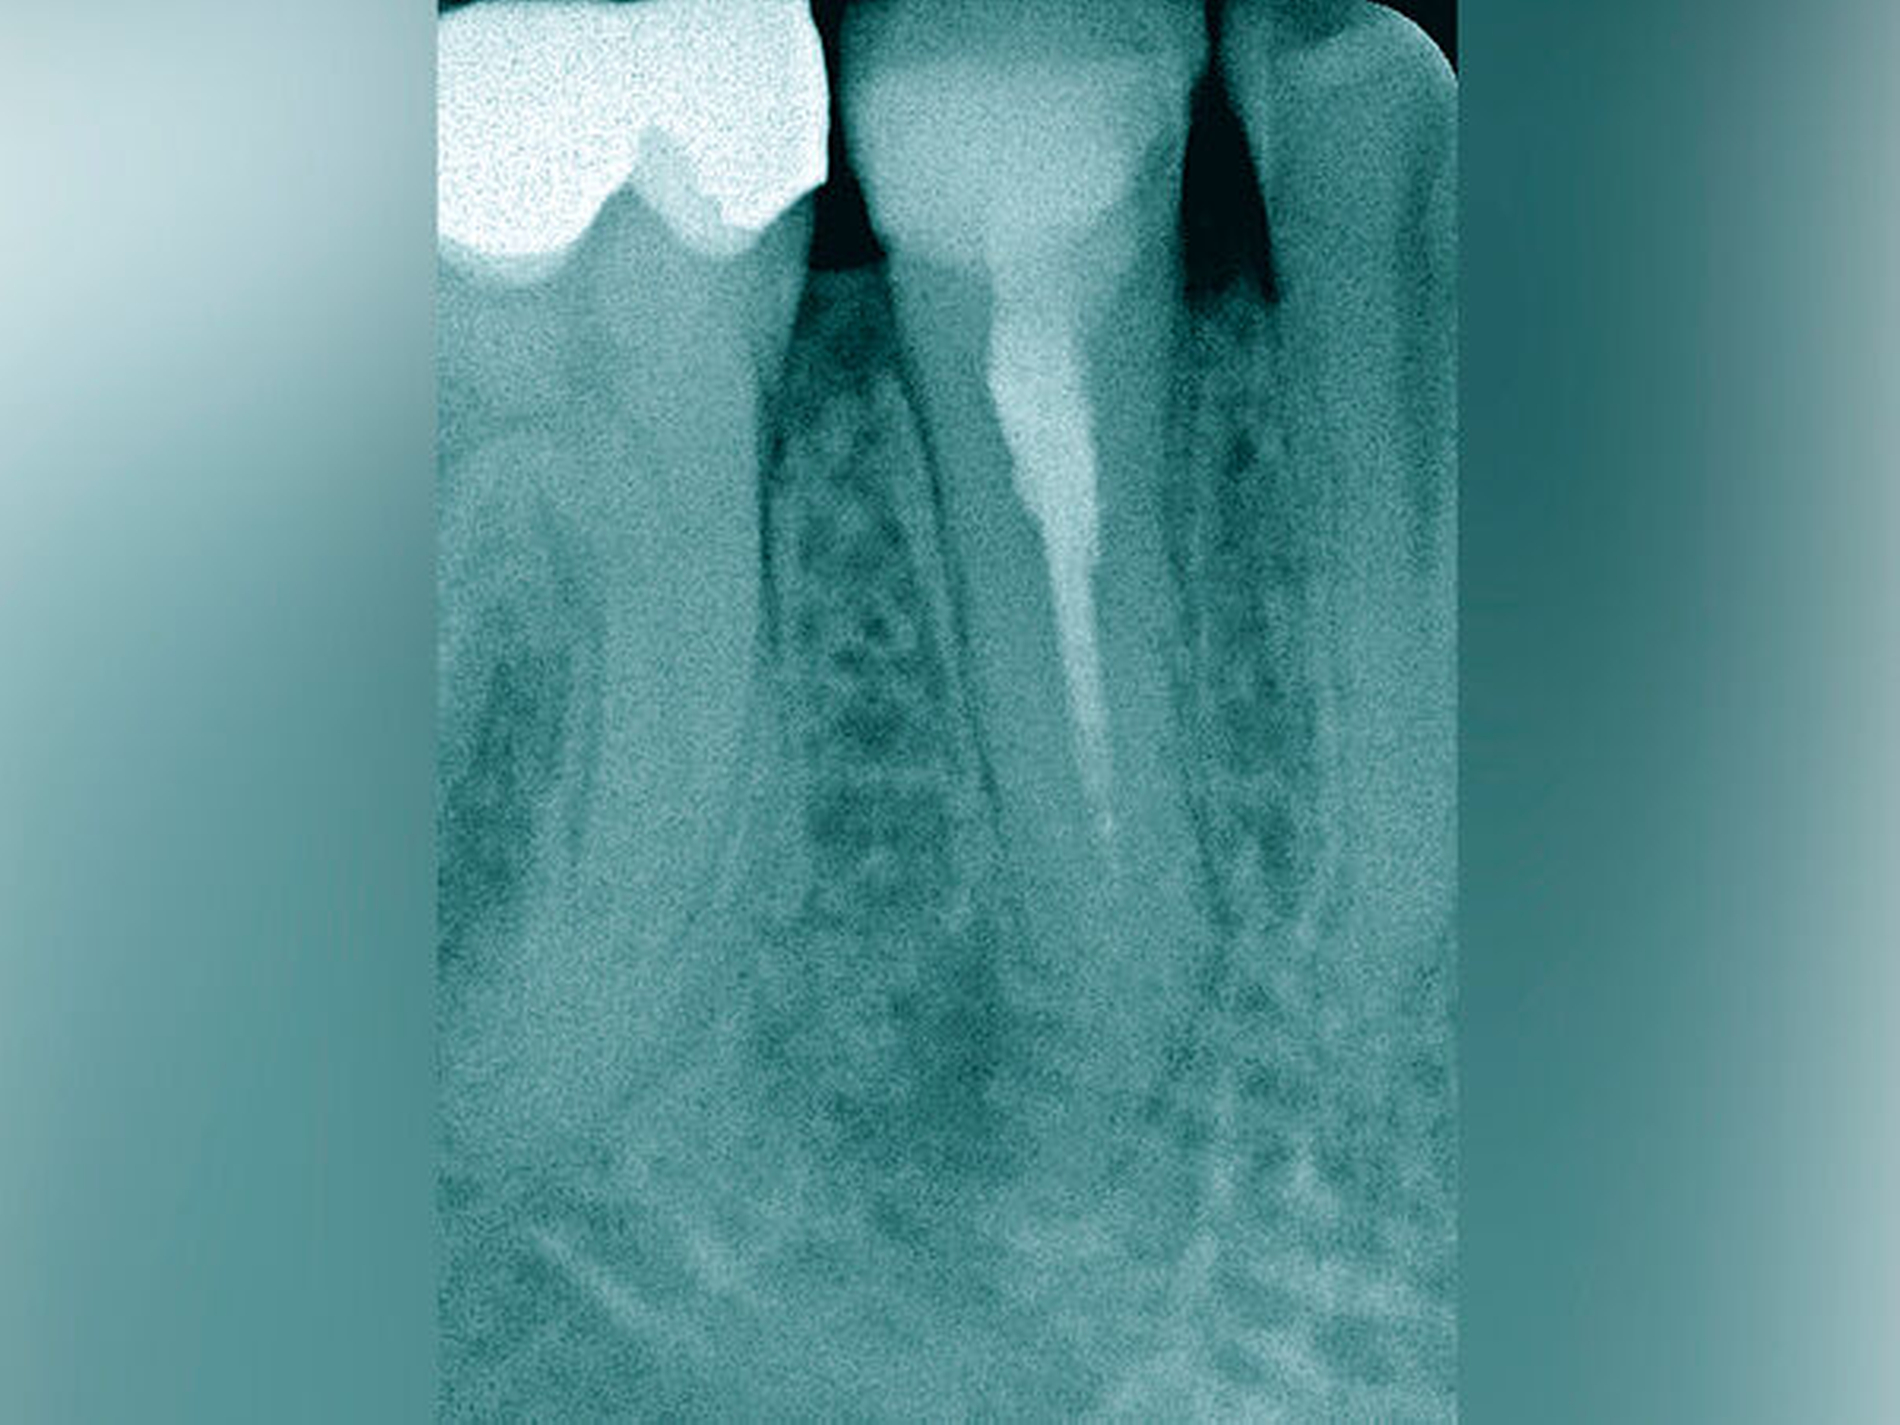

Jede erforderliche endodontische Revision ist eine Summe von mehreren endodontischen Problemstellungen, die die Grenzen einer bisher unter normalen zahnärztlichen Bedingungen möglichen Wurzelkanalbehandlung aufzeigt. Eine Korrektur ist meist nur unter Zuhilfenahme spezieller Hilfsmittel und einer optimalen optischen Vergrößerung möglich (Abbildung 5) [Imura et al., 2007; Naito, 2010].